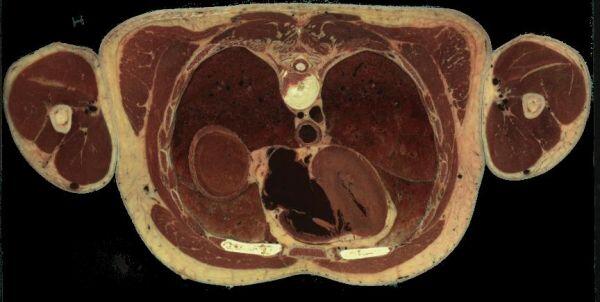

à 463 mm du sommet du crane, les mêmes organes avec toujours aorte et oesophage, au centre, devant la vertèbre :